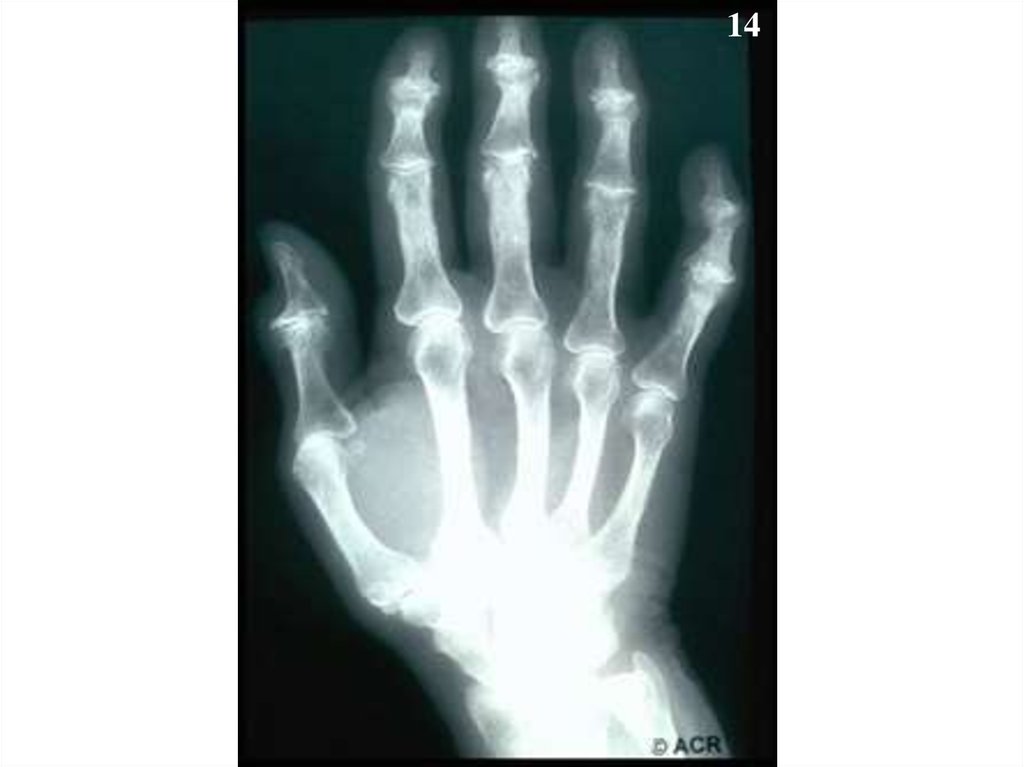

14.

14